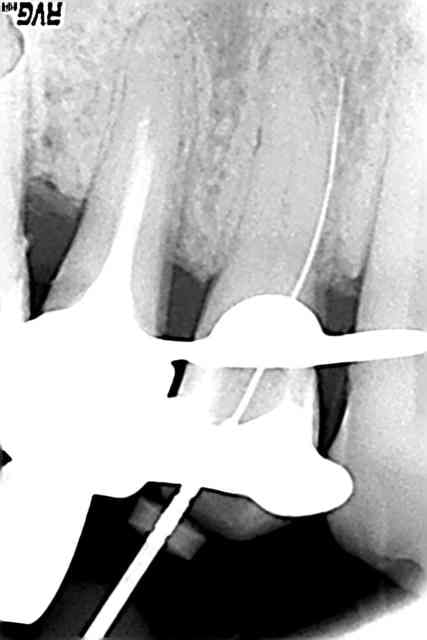

J'ai les boules... J'ai fait une belle cavité à 4 parois, j'ai mis une digue neuve... et voilà... :-(

Perfo jard n9wph1 - Eugenol

Wolford hm5yx3 - Eugenol